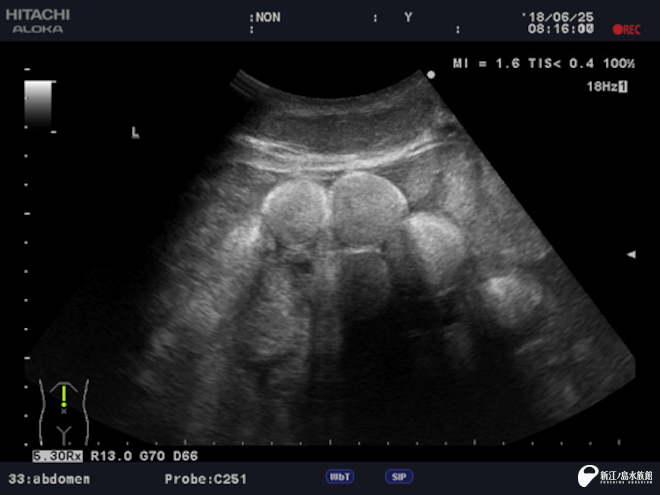

これは超音波診断装置。

高い周波数の音波を体内に照射し、組織から跳ね返ってくる反射波をリアルタイムで画像化する装置です。お腹の中にいる赤ちゃんのようすや、腸の蠕動(ぜんどう)運動、腎結石などさまざまな症状を見ることができます。

えのすいでは 3台の機器を持っていて、その時の動物の状況によって使い分けています。液晶画面が付いているものや、映像をリアルタイムにスマートフォンで見ることができるワイヤレスのものなど使用目的によって使い分けています。

2018年 アオウミガメ「ノンキ」の卵胞エコー。丸く映っているのが卵胞です。